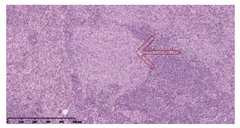

| INH-RFP (2 w) + AEC/BC02 (3 doses) | ![]() Arrows indicate granulomatous lesions | ![]() Arrows indicate granulomatous lesions | ![]() Arrows indicate granulomatous lesions |

| INH-RFP (4 w) + AEC/BC02 (3 doses) | ![]() No granulomatous lesions | ![]() Arrows indicate granulomatous lesions | ![]() Arrows indicate granulomatous lesions |

| INH-RFP (2 w) + AEC/BC02 (6 doses) | ![]() Arrows indicate granulomatous lesions | ![]() Arrows indicate granulomatous lesions | ![]() Arrows indicate granulomatous lesions |

| INH-RFP (4 w) + AEC/BC02 (6 doses) | ![]() Arrows indicate granulomatous lesions | ![]() Arrows indicate granulomatous lesions | ![]() Arrows indicate granulomatous lesions |

| INH-RFP (2 w) | ![]() Extensive granulomatous lesions | ![]() Extensive granulomatous lesions | ![]() Arrows indicate granulomatous lesions |

| INH-RFP (4 w) | ![]() Granulomatous lesions in the middle | ![]() Extensive granulomatous lesions | ![]() Arrows indicate granulomatous lesions |

| AEC/BC02 (3 doses) | ![]() Extensive granulomatous lesions | ![]() Large granulomas lesions on both sides | ![]() Extensive granulomatous lesions |

| AEC/BC02 (6 doses) | ![]() Extensive granulomatous lesions | ![]() Extensive granulomatous lesions | ![]() Extensive granulomatous lesions |

| NS | ![]() Extensive granulomatous lesions | ![]() Extensive granulomatous lesions | ![]() Extensive granulomatous lesions |